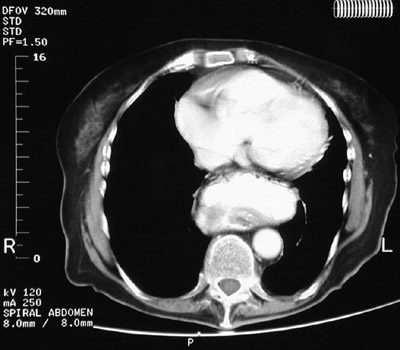

| The chest CT scan shown here demonstrates another hiatal hernia with a dilated portion of gastric fundus extending through a widened esophageal hiatus into the lower chest. Many hiatal hernias are associated with gastroesophageal reflux--but not all. Many cases of gastroesophageal reflux are associated with a hiatal hernia--but not all. |